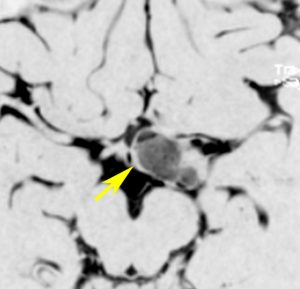

視索に限局する毛様細胞性星細胞腫

左の視索の内部から発生したもので,これも単神経・視神経膠腫と同様によくみるものです。左の画像で視神経交叉が全く侵されていないのがわかります。

単視神経膠腫は全摘出できるのですが,このタイプは外側膝状体へ及ぶので完全摘出ができません。部分摘出と定位放射線治療が適応となります。